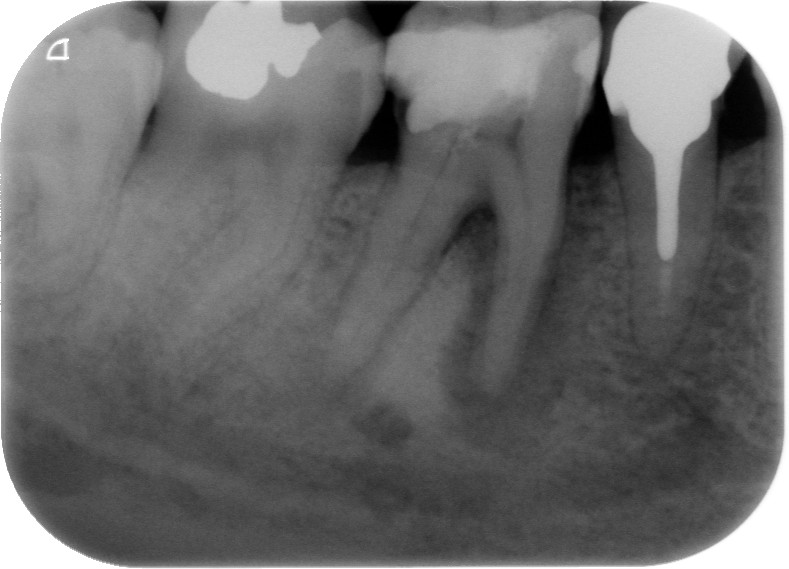

Fig. 1 : Radiographie préopératoire montrant la présence d’une reconstitution corono-radiculaire coulée, ancrée dans les trois canaux.

Fig. 2 : Contrôle radiographique en vue d’évaluer l’axe de délogement de la reconstitution corono-radiculaire, ce qui a permis de corriger l’angle de coupe.

D’un point de vue pratique, la première étape consiste à réduire les dimensions du tenon s’il occupe une grande partie de la structure coronaire, de préférence en lui donnant une forme cylindrique similaire à celle d’un tenon préfabriqué. De même, une reconstitution corono-radiculaire coulée ancrée dans plusieurs canaux doit d’abord être sectionnée jusqu’au niveau du plancher de la cavité pulpaire, afin de la traiter comme un ensemble de tenons unitaires, ce qui diminue le degré de rétention global du système. La réduction du tenon doit être effectuée avec des fraises en carbure spécialement conçues pour découper le métal, sous une irrigation abondante. Les évaluations cliniques et radiographies préliminaires sont essentielles pour planifier l’angle de coupe. La procédure doit être fréquemment vérifiée et, si nécessaire, il convient d’effectuer des contrôles radiographiques avant qu’une quantité excessive de dentine ne soit sacrifiée (Figs. 1–3).